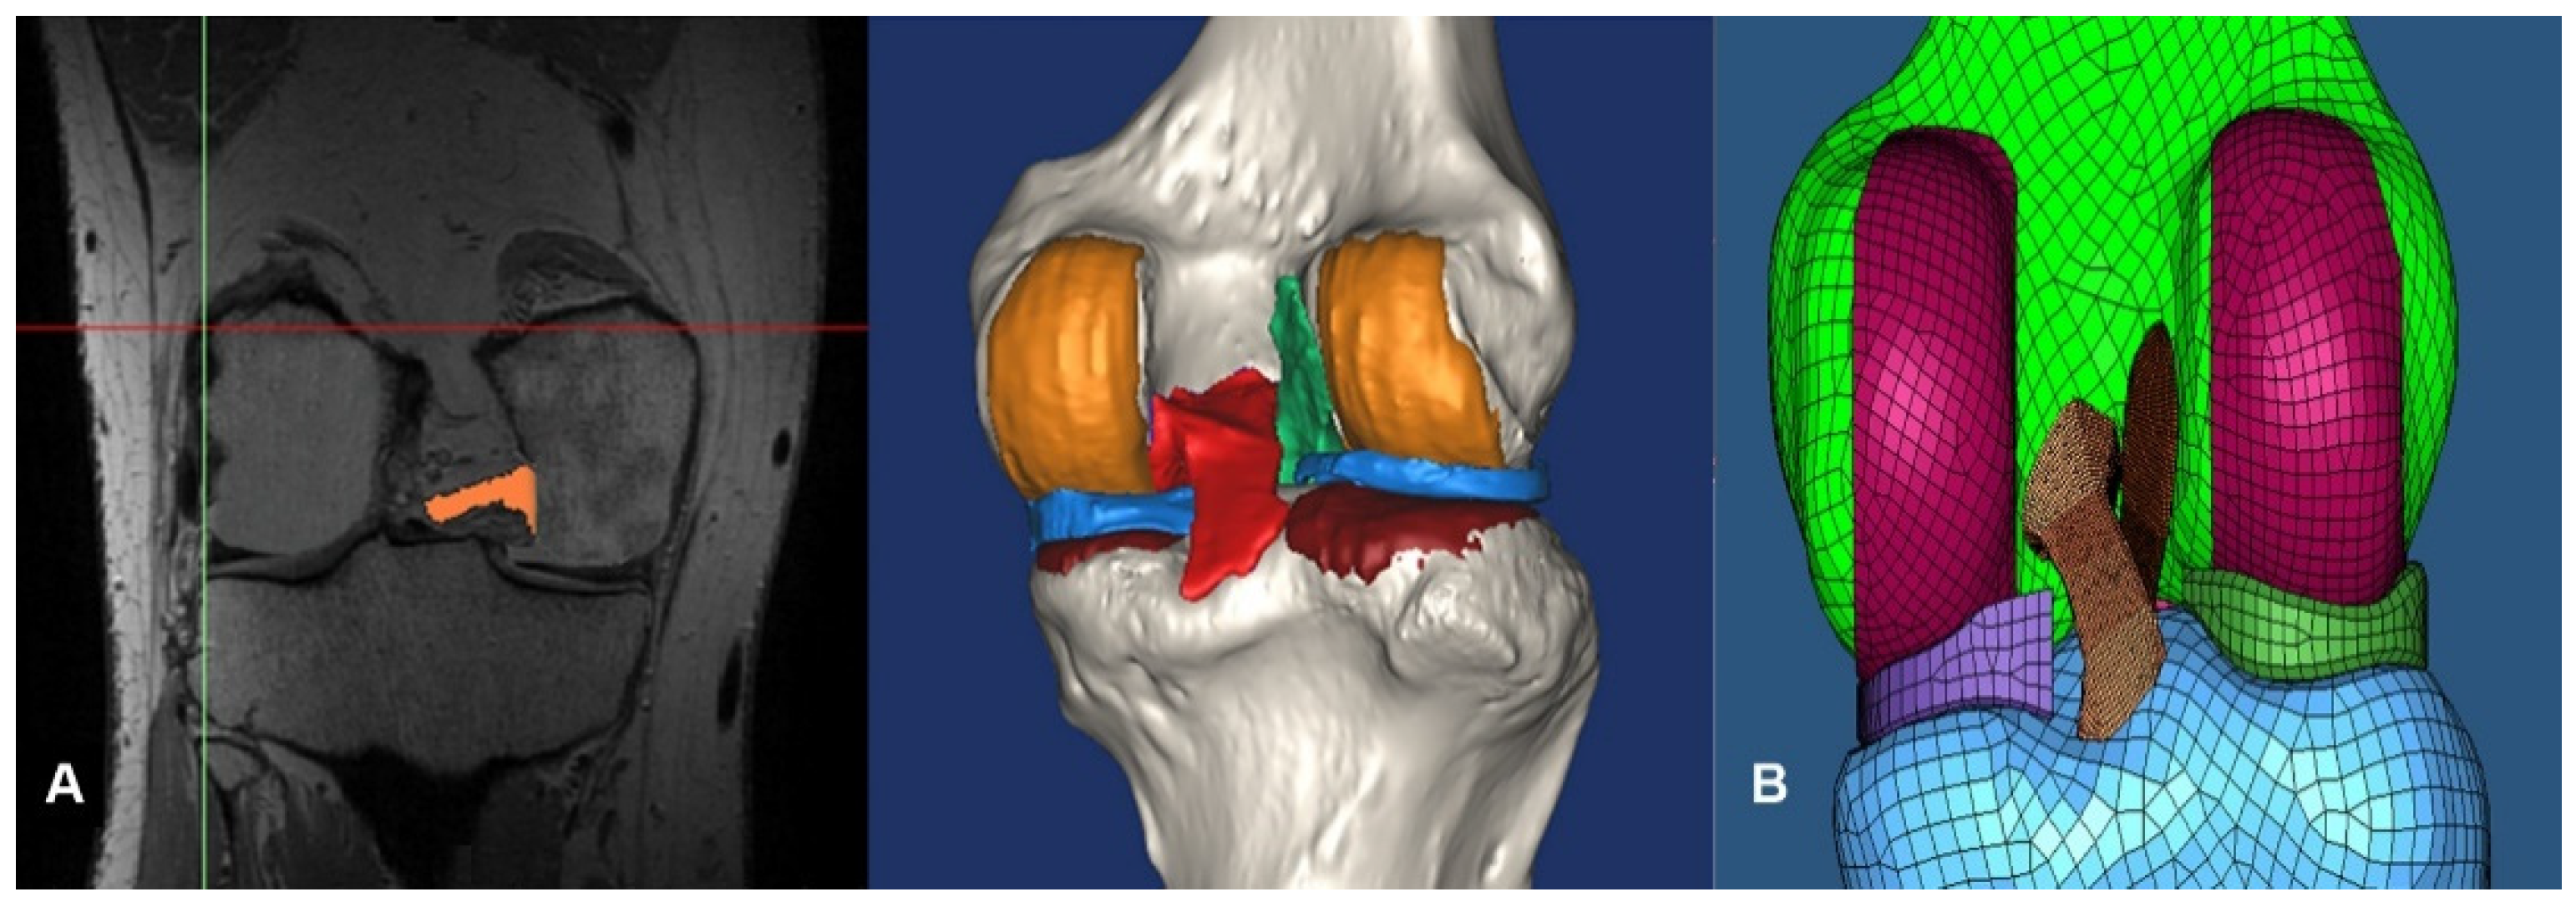

2.1. Intact Model

2.3. Surgical Simulation Model